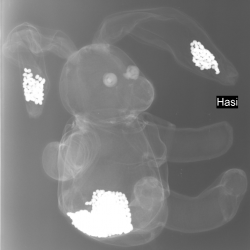

Erst das Kuscheltier - dann das Kind

Galerie der Kuscheltiere

Kinder kommen oft sehr ängstlich mit Kuscheltieren oder Puppen zum Röntgen. Um den Kindern diese Angst zu nehmen, kann man vor deren neugierigen Augen, zuerst die kuscheligen Begleiter unter die Röhre legen.

Spätestens wenn die Kinder die Bilder Ihrer Kuscheltiere sehen ist die Angst vorm Röntgen meist vergessen. So wie bei den unten abgebildeten Bildern.

Galerie wird ständig erweitert!